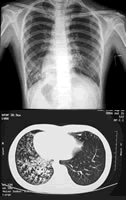

实验室检查 血常规大致正常,血气正常。Ig系列、CD系列、分泌型IgA均在正常范围。心电图示右位心。超声心动图示:镜向右位心,余心内结构未见明显异常。腹部B超:脏器转位(肝、胆、胰、脾)。柯瓦位X线片:副鼻窦炎。X线胸片:肺内间质+实质改变,右位心(图1)。胸部CT:左肺舌叶及右下肺间质+实质病变,右下肺支气管扩张(支扩)形成,右位心(图2)。

于飞鸿医师 本病例特点:(1)青春期女孩,慢性起病,病程迁延。(2)以反复咳嗽,流涕,咳痰为主要表现。自幼每年反复患上呼吸道感染和支气管肺炎。(3)自新生儿期起反复患中耳炎。(4)否认家族遗传病史。(5)查体双肺呼吸音粗,有少许喘鸣音,右下肺有中水泡音。心脏右位,心界不大,心律齐。肝脾不大,双手杵状指。(5)辅助检查:血常规、血沉、C反应蛋白、支原体抗体、PPD均阴性。心电图、超声心动图、X线胸片、胸部CT均提示右位心。柯瓦位片示副鼻窦炎。胸部CT示肺内间质+实质病变,右下肺支扩形成。腹部B超示内脏转位。根据患儿的上述特征,诊断反复呼吸道感染成立,尚需完善相关检查,寻找基础疾病。